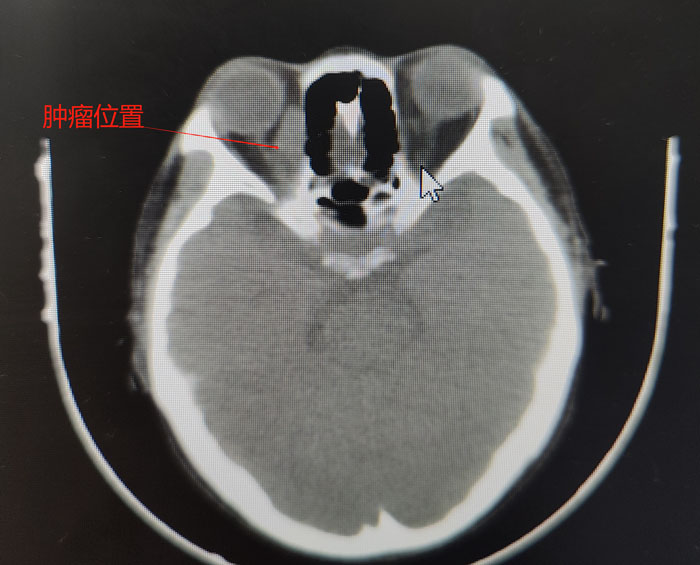

患者的病情非常特殊,其眼眶肿物内下方距离眶缘1cm处有一根较大的动脉血管,而肿瘤内侧又紧挨着眼球,一旦穿刺出血,在患者血小板及白细胞危急值的状态下开眶止血,无疑是难上加难。其次,术后暴发感染的风险也难以控制。同时,穿刺是为了更好地明确病理,需要选用粗针,这又极大增加了穿刺风险……面对如此复杂的形势,在眼科肿瘤团队和纪晓惠主任医师的配合下,确定穿刺位置和进针方向、深度,经过三次“惊心动魄”的穿刺,顺利取出三条鱼肉状肿物组织,病理诊断后,疾病的“真容”终于露出水面,患者确诊为非霍奇金弥漫大B淋巴瘤。噬血细胞综合征考虑为淋巴瘤继发,需要积极控制淋巴瘤原发病。之后,患者前往我院血液中心接受进一步规范化精准治疗。